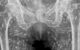

Ποστάροντας στο Χ, ο επαγγελματίας υγείας Sam Ghali μοιράστηκε την «πιο τρελή ακτινογραφία που έχω δει ποτέ», επισημαίνοντας τα πολυάριθμα ασβεστοποιημένα αυγά ταινίας που ήταν διάσπαρτα στη λεκάνη του ασθενούς.

Σύμφωνα με τον γιατρό, ο άνδρας δεν είχε γνωρίσει ποτέ την πάθηση και προσήλθε για ακτινογραφία μόνο αφού αντιμετώπισε πόνο στο ισχίο. «Πρόκειται για μια πάθηση γνωστή ως κυστικέρκωση, ουσιαστικά πρόκειται για προνυμφικές κύστεις του taenia solium, γνωστού και ως χοιρινού ταινιοσκώληκα», ανέφερε ο Ghali στην πλατφόρμα κοινωνικής δικτύωσης.

Και πρόσθεσε: «Αυτές οι κύστεις μπορούν να ταξιδέψουν οπουδήποτε σε ολόκληρο το σώμα, κυρίως στους μυϊκούς και μαλακούς ιστούς των γοφών και των ποδιών. Η κατάσταση αυτή προέρχεται όταν ο ασθενής τρώει κακοψημένο ή ωμό χοίρο. Αν βρίσκονται μόνο στη λεκάνη, δεν αποτελούν απειλητικό για τη ζωή πρόβλημα. Το πρόβλημα είναι αν ταξιδέψουν στον εγκέφαλο και κατακάτσουν εκεί.